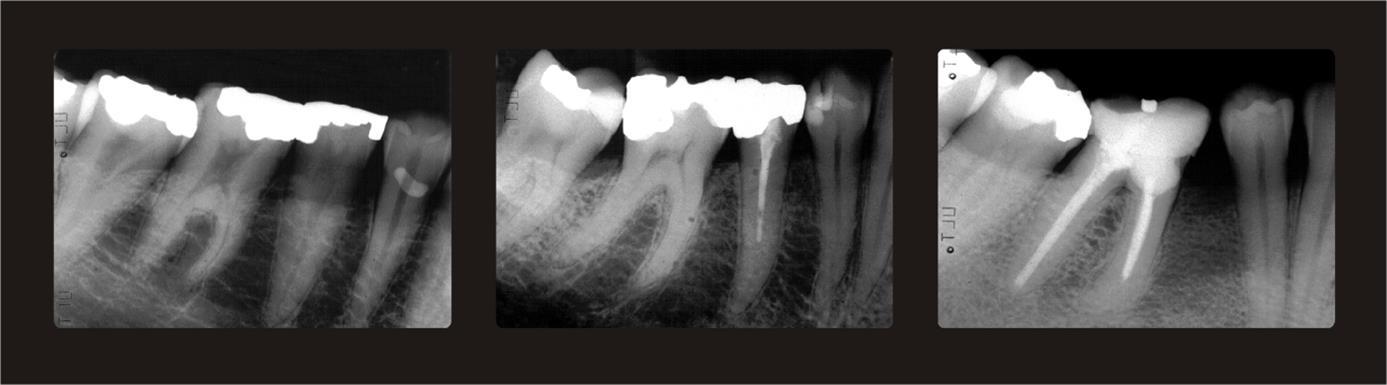

Three periapical and three panoramic radiographs with varying degrees of trabeculation were used as index references to assess the trabeculation pattern as proposed by Lindh et al. in 199611 and modified by Jonasson et al. 2001.4 The periapical radiographs are shown in Figure 1. Periapical radiographs are more easily interpreted than panoramic radiographs, which demand training (Pham et al 2010).12 With the help of these radiographs, the trabeculation of the mandibular alveolar process was classified as either sparse (regarded as an ordinal variable with the value 1), mixed dense and sparse trabeculation (value 2) or dense (value 3). Sparse trabeculation had large intertrabecular spaces apparent in most of the alveolar processes, particularly in the crestal dentate premolar area. Dense trabeculation had small intertrabecular spaces everywhere. Mixed dense and sparse trabeculation was dense crestally and sparser apically. In the event of uncertainty, the mixed category was chosen (Figure 1).

Figure 1.Periapical reference radiographs.Left: Sparse trabeculation with large intertrabecular spaces and almost invisible trabeculae. Middle: Mixed dense and sparse trabeculation with small intertrabecular spaces cervically and larger spaces more apically. Right: Dense trabeculation with small intertrabecular spaces.